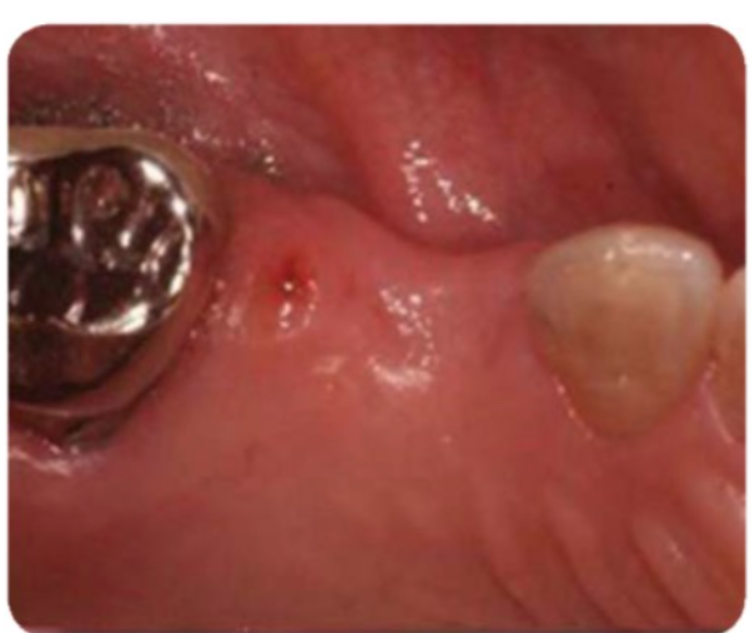

Bệnh nhân đến phòng khám với tình trạng viêm nướu do mảng bám kèm theo biến dạng niêm mạc-nướu ở sống hàm mất răng. Bệnh nhân tiêu xương nhẹ theo chiều đứng ở mào xương tại vị trí #14. Kế hoạch điều trị cho bệnh nhân này là điều trị ban đầu bao gồm cạo vôi răng và hướng dẫn vệ sinh răng miệng để giải quyết viêm nướu. Tiếp theo là phẫu thuật tái tạo xương có hướng dẫn GBR để khắc phục thiếu hồng ngoài-trong của sống hàm. Sau khi vị trí ghép đã lành thương, tiến hành đặt implant. Sau khi đủ thời gian tích hợp xương thì làm phục hình trên implant.

Sau giai đoạn điều trị ban đầu, bệnh nhân bắt đầu điều trị GBR. Nhịp cầu trước đó đã được cắt và lấy ra trước phẫu thuật.

Tình trạng sau khi tháo nhịp cầu (mặt nhai)